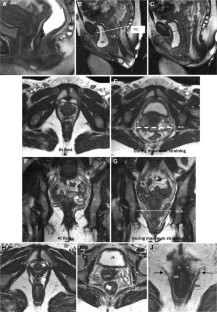

Fig. 2